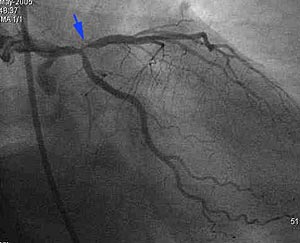

This patient, with a strong family history, had an episode of chest pain a month ago with an equivocal stress test. The cardiac CT (A, B) shows a severe stenotic lesion in the proximal LAD (blue arrows), which was confirmed on the catheter angiogram (C) and the patient was successfully stented.